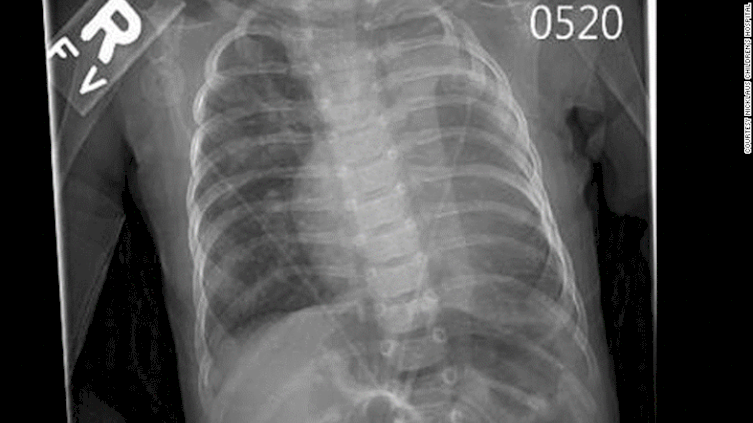

2. Sayangnya setelah lahir, Teegan terdeteksi memiliki jantung yang tak normal dan separuh paru-paru.

6. Lewat perangkat Google Cardboard dan teknologi virtual reality, Muniz memvisualisasikan organ jantung Teegan ke dalam bentuk tiga dimensi, memetakan langkah-langkah yang tepat. Dengan begitu mereka dapat melihat dan memeriksa jantung dari berbagai sudut untuk kemudian dilakukan tindakan operasi.

7. Teegan selamat! Operasi berjalan lancar dan para dokter yang terlibat mengklaim, jika bukan karena Google Cardboard mereka tak akan mampu memvisualisasikan jantung dengan cara yang efektif.